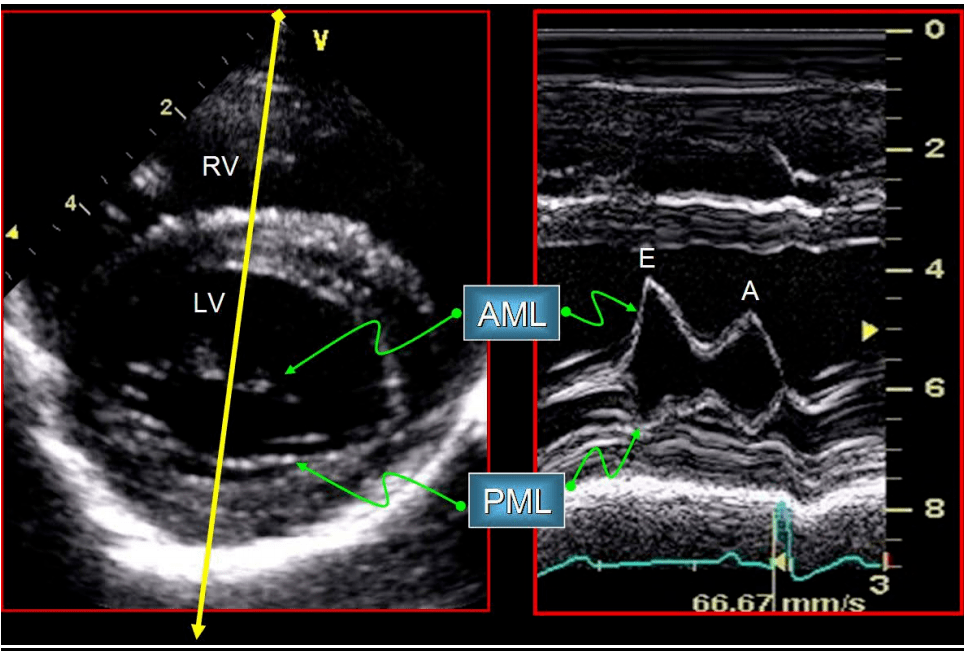

(1)胸骨旁左心室长轴切面:显示a2,p2,(图5a);(2)二尖瓣水平短轴切面